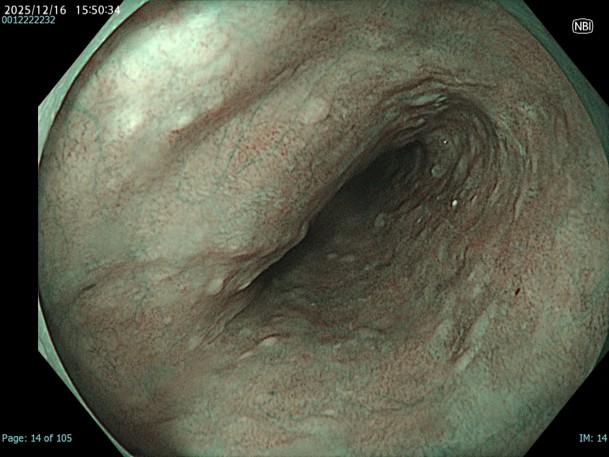

• NBI観察(中遠景)

強調設定:A8

図2

NBIにすることで白色光観察と比較して同部位の粘膜粗造が目立つ。一方で色調変化は軽度でDLも部分的には認識できるが、不明瞭な部分もあり、正確な領域評価が難しい。